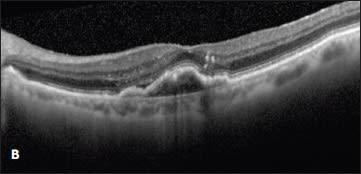

Figure 5. A patient with a serous PED was observed at presentation (A) and developed subretinal fluid three months later (B). Treatment was offered at three months, but the patient declined until a PED developed in the fellow eye 13 months later (C). At that time, the patient underwent intravitreal treatment with bevacizumab, with resolution of the subretinal fluid and a decrease in height of the PED (D). The patient’s vision was 20/32 both before and after treatment.

Case 5. The desire to avoid the risk of an RPE tear led one patient to refuse anti-VEGF therapy for more than a year and a half. This 69-year-old man presented with a large serous PED in the right eye, resulting in decreased vision from 20/20 to 20/126 (Figure 5A). There was no associated intraretinal or subretinal fluid on OCT, and due to the ability to correct his vision comfortably with a hyperopic refraction, observation with close follow-up was chosen.

Three months later, his vision remained 20/32, but subretinal fluid was noted on OCT (Figure 5B). Treatment was recommended, but the patient refused therapy. On multiple return visits, the patient continued to decline treatment. Sixteen months after his initial presentation, he developed metamorphopsia in his left eye, and a new serous PED was seen on OCT. The PED in his right eye had a stable cuff of subretinal fluid (Figure 5C).

At this point the patient consented to treatment with intravitreal bevacizumab in the right eye. After three injections, the subretinal fluid resolved, and the PED decreased slightly in apical height (Figure 5D). His vision remained unchanged at 20/32 throughout treatment.